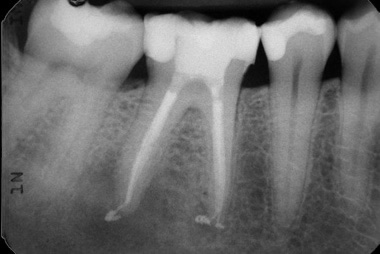

Patients usually experience pain on biting and sensitivity on hot and cold although not always. The main way of diagnosing treatment is by taking x-rays. Infection is shown around the tip of the roots or by decay going through to the nerve. Depending on the level of pain or if any swelling is present antibiotics may be prescribed prior to treatment.

The procedure itself is carried out under a local anaesthetic. Once you are numb and ready to commence we access the canals by drilling into the tooth. The infection is removed and the canals cleaned and shaped using special files. Whilst we are doing this the canals are continuously irrigated using a special solution to help remove any bacteria.

Once the tooth has been cleaned and is free from infection a special root filling is placed into the canals. The tooth is then restored with a permanent filling. A crown is usually advised to protect the tooth as having Root Canal Treatment can weaken the tooth.